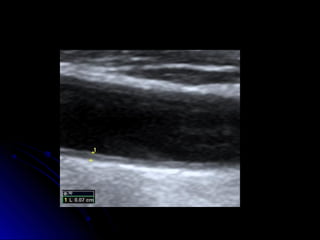

Complexo médio-intimalComplexo médio-intimal

Espessamentos do complexo média-

íntima estão relacionados com maior risco

de eventos isquêmicos agudos

coronarianos e AVC

Bots, ML et al. Circulation, Sep 1997; 96: 1432 - 1437

Pignoli P. Circulation. 1986 Dec;74(6):1399-406.